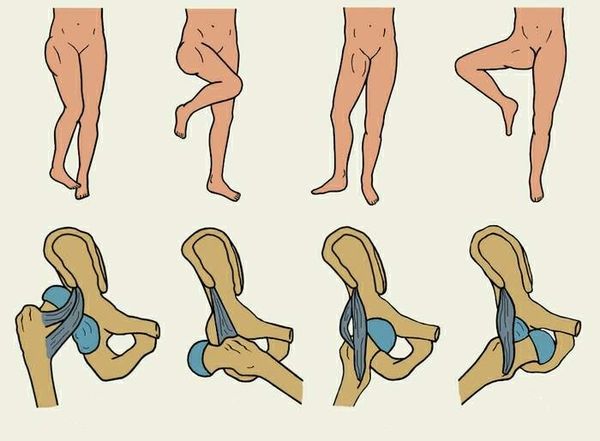

Положение ноги в момент травмы определяет, куда сместится головка бедра при вывихе. В соответствии с этим выделяют:

- подвздошный (задне-верхний) вывих — при ударе головка бедра направляется вверх, к подвздошной кости, так как до этого нога была приведена (т. е. немного подтянута к туловищу) и выпрямлена;

- седалищный (задне-нижний) вывих — головка бедра смещается назад, к седалищной кости; возникает, если нога была приведена и согнута;

- лонный (передне-верхний) вывих — головка бедра смещается вперёд, к лобковой кости; формируется, если нога была отведена вбок и выпрямлена;

- запирательный (передне-нижний) вывих — головка бедра смещается вниз и вперёд, к запирательному отверстию таза; возникает, если нога была отведена вбок и согнута.

Виды вывихов бедра

Передние вывихи встречаются в 10 % случаев, все остальные вывихи являются задними [17]. Патологические вывихи классифицируют по такому же принципу.